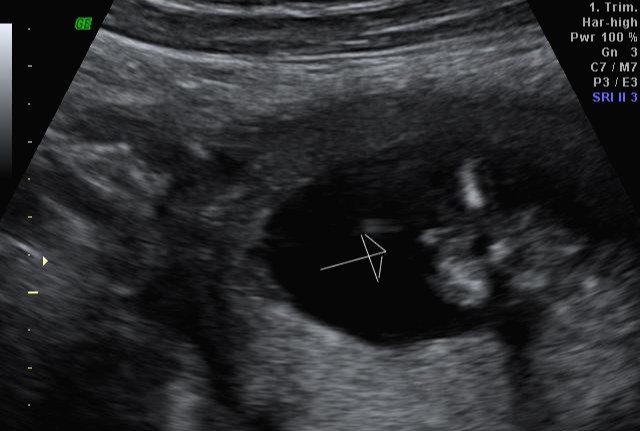

임신 20주 정밀 초음파 검사 : 성별 반전

20주 정밀초음파를 받았는데 아이 건강상태를 꼼꼼하게 확인하고 마지막으로 성별을 확인했는데 딸이라고... 저에게 성별 반전이 있었어요~ 그래서 믿을 수가 없어서 제가 초음파 검사를 했을 때마다 아들이라고 했는데 지금 딸이라 해서 너무 혼란스럽다고 하니 다시 누워보라며 다시 봐주셨는데 역시나 딸 ^^~ 확실한 성별 반전! 딸을 더 원했던 남편은 저의 기분을 생각하지 않고 너무 행복해하더라고요 ㅋㅋㅋㅋㅋ ;;

성별이 중요하진 않지만... 이미 받은 선물들도 있고 아들이라고 해서 좋아했던 가족들에게 너무 미안해서 혼자서 훌쩍훌쩍... 눈물을.....;;;; 그리고 감정을 추스르고 가족에게 전화를 해서 딸이라고 말을 하니 성별이 뭐가 중요하냐고 너무 이쁘겠다며 요즘은 딸이 최고라고 하면서 저의 기분을 달래주셔서 미안한 마음과 고마운 마음이 동시에 들었어요~!